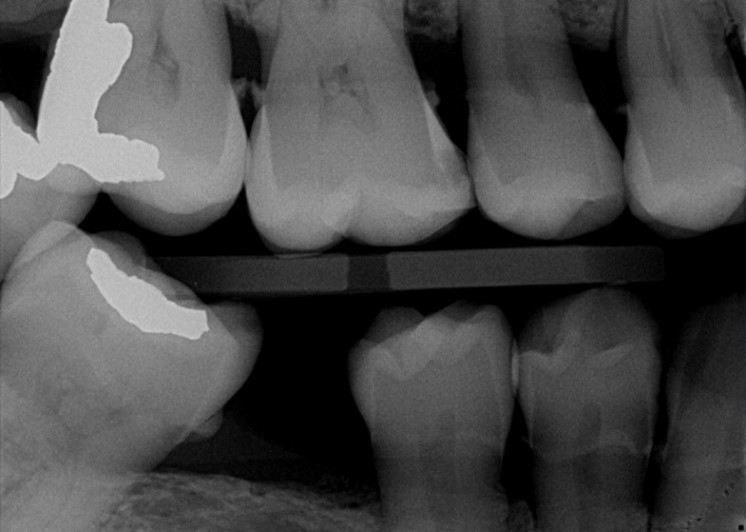

Through years of training, our dentists are experts in reading imaging results, able to see decay, cavities and more on your X-rays. For the lay person, these results are often much more difficult to interpret, even when the dentist is pointing out what he or she is seeing. OVERJET technology analyzes the X-ray images similar to how the dentist would, then overlays that image with colored highlighting and measurements to illuminate any diseases, conditions and more. Essentially, this allows our patients to see what the dentist sees!

Xray

X-Ray